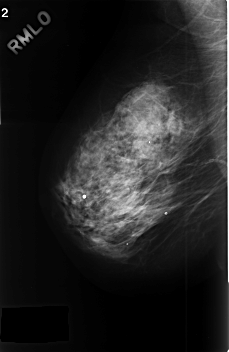

ics_version 1.0 filename C-0379-1 DATE_OF_STUDY 23 4 1996 PATIENT_AGE 67 FILM FILM_TYPE REGULAR DENSITY 3 DATE_DIGITIZED 3 11 1998 DIGITIZER LUMISYS LASER SEQUENCE LEFT_CC LINES 4520 PIXELS_PER_LINE 3008 BITS_PER_PIXEL 12 RESOLUTION 50 OVERLAY LEFT_MLO LINES 4504 PIXELS_PER_LINE 3016 BITS_PER_PIXEL 12 RESOLUTION 50 OVERLAY RIGHT_CC LINES 4568 PIXELS_PER_LINE 2936 BITS_PER_PIXEL 12 RESOLUTION 50 NON_OVERLAY RIGHT_MLO LINES 4568 PIXELS_PER_LINE 2968 BITS_PER_PIXEL 12 RESOLUTION 50 NON_OVERLAY |